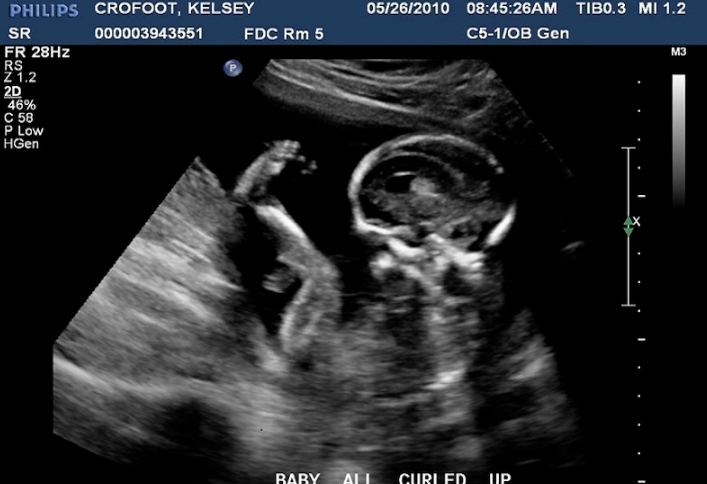

Siêu âm 2D là kỹ thuật siêu âm thai cho kết quả hình ảnh hiển thị các mặt cắt của cơ thể trong không gian 2 chiều, theo thang màu đen và trắng.

Dựa vào kết quả siêu âm 2D, bác sĩ có thể xác định phụ nữ có mang thai hay không, tuổi thai, vị trí thai, số nhịp tim thai và chuyển động của bé. Ngoài ra, khi siêu âm, bác sĩ cũng có thể phát hiện được các dấu hiệu bất thường của thai nhi để có hướng xử lý kịp thời.

Sau khi siêu âm thai, mẹ sẽ nhận được tấm phim tiêu bản. Nhưng để hiểu được kết quả siêu âm, mẹ sẽ cần đến sự giải thích của bác sĩ mới nhận ra các chỉ số cơ thể của bé và những đặc điểm của con. Cũng vì thế mà nhiều mẹ bầu cảm thấy nghi ngờ tính chính xác của loại siêu âm này.